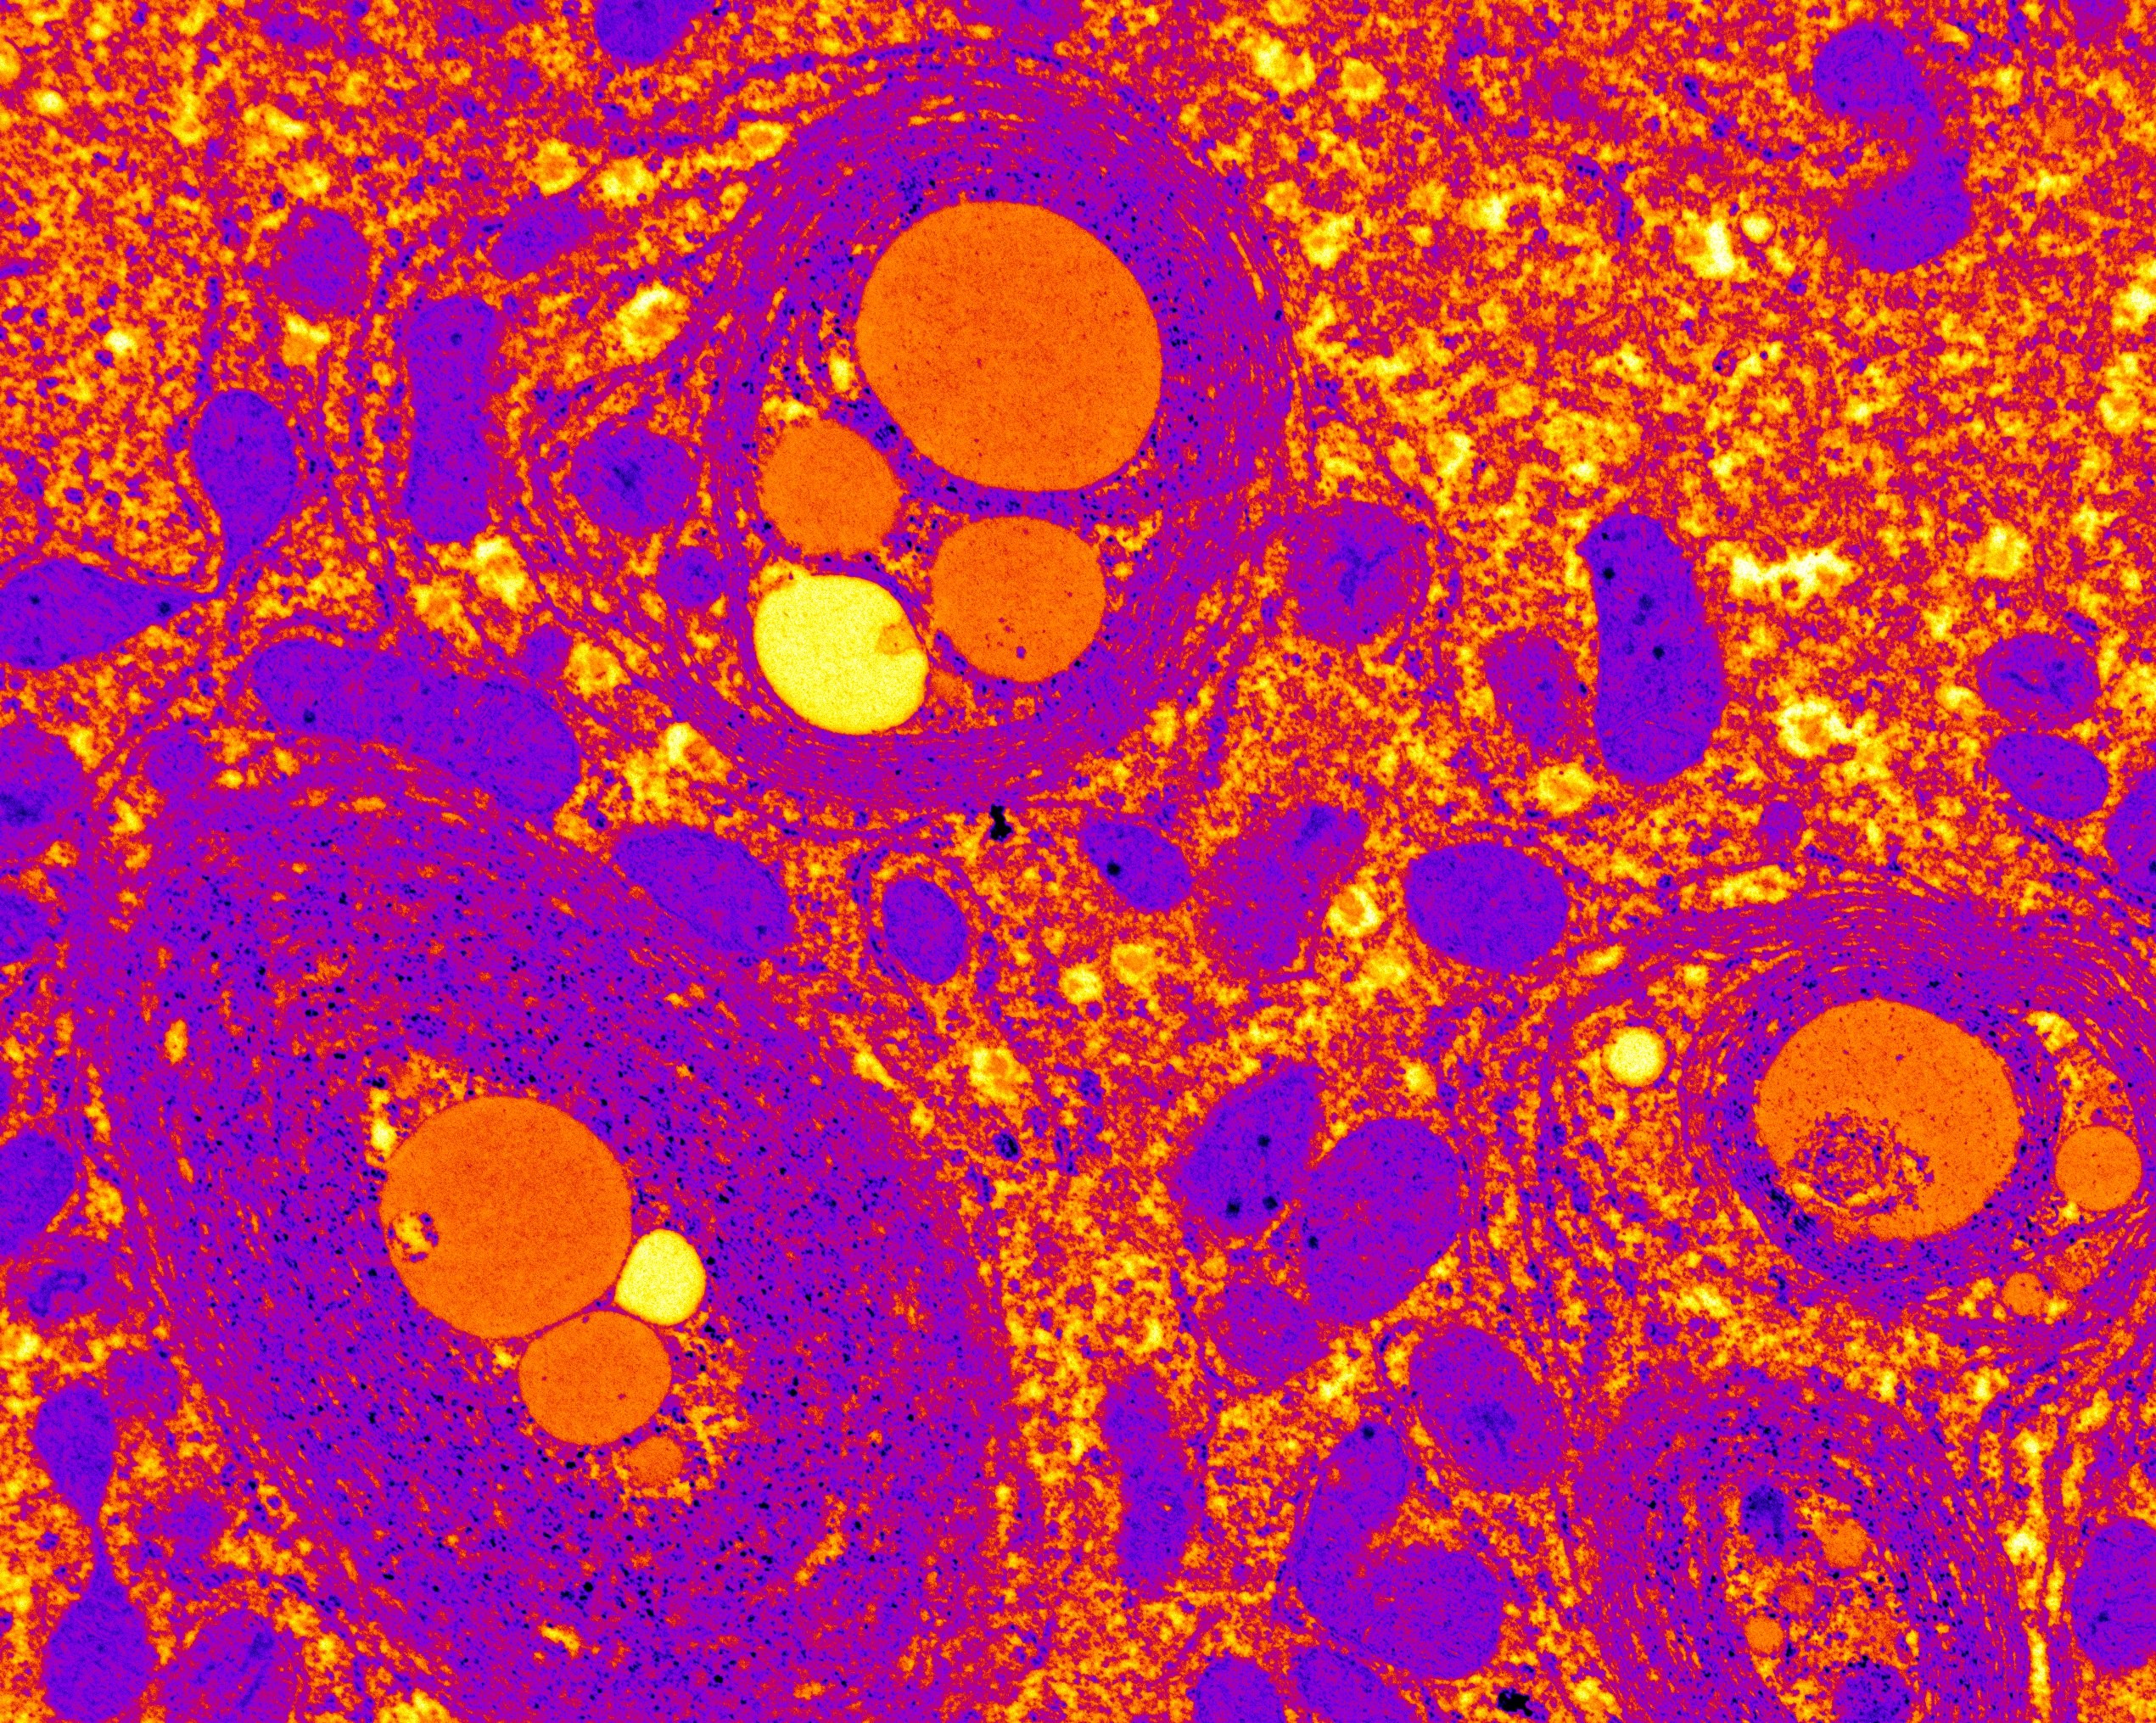

Las células gliales defectuosas se vinculan al Parkinson